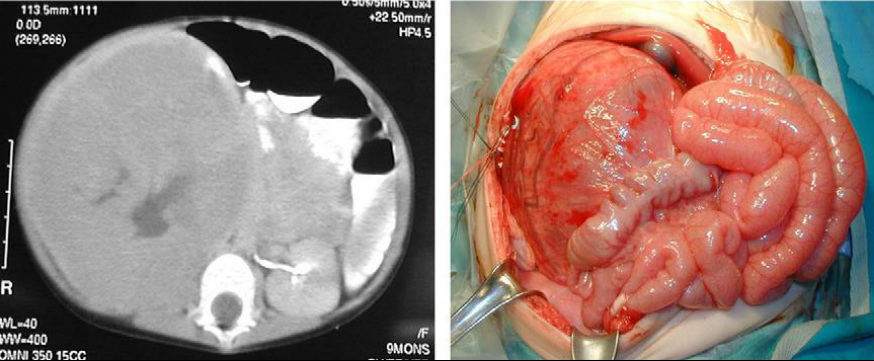

File:Wilms.jpg